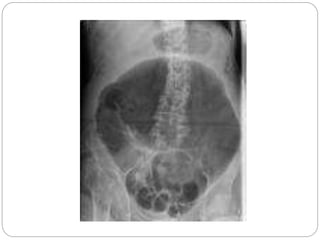

 Chest x-ray-

 Abdominal film-

o Duodenal ileus

o Gasless abdomen

o “colon cut off” sign

o Renal “halo” sign

o Absent left psoas shadow

o Indistinct mottled shadowing

o Sentinel loop

o Intrapancreatic gas-abscess/ enteric fistula